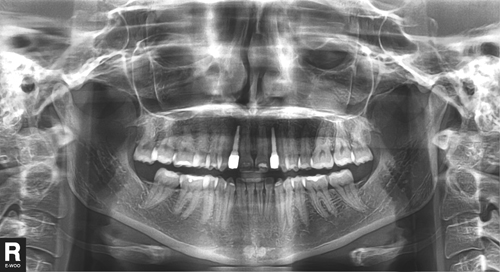

En la panorámica se observa la presencia de ambos 3º molares superiores y la agenesia de los inferiores así como de los laterales motivo de la consulta , y en la rx simple en proyección dorso palmar de su mano, observamos el cierre de todas las fisis o cartílagos de crecimiento, lo que indica una maduración esquelética completa.

Se presenta la paciente en el año 2007, con una hipodoncia reflejada en la agenesia de ambos laterales superiores y ambos terceros molares inferiores, portando PPR que reemplaza ambos laterales derivado por colega ortodoncista.

Decidimos entonces tomar una nueva panorámica y realizar un Índice de Scarpa para corroborar su edad ósea.

O.P.M. postoperatoria